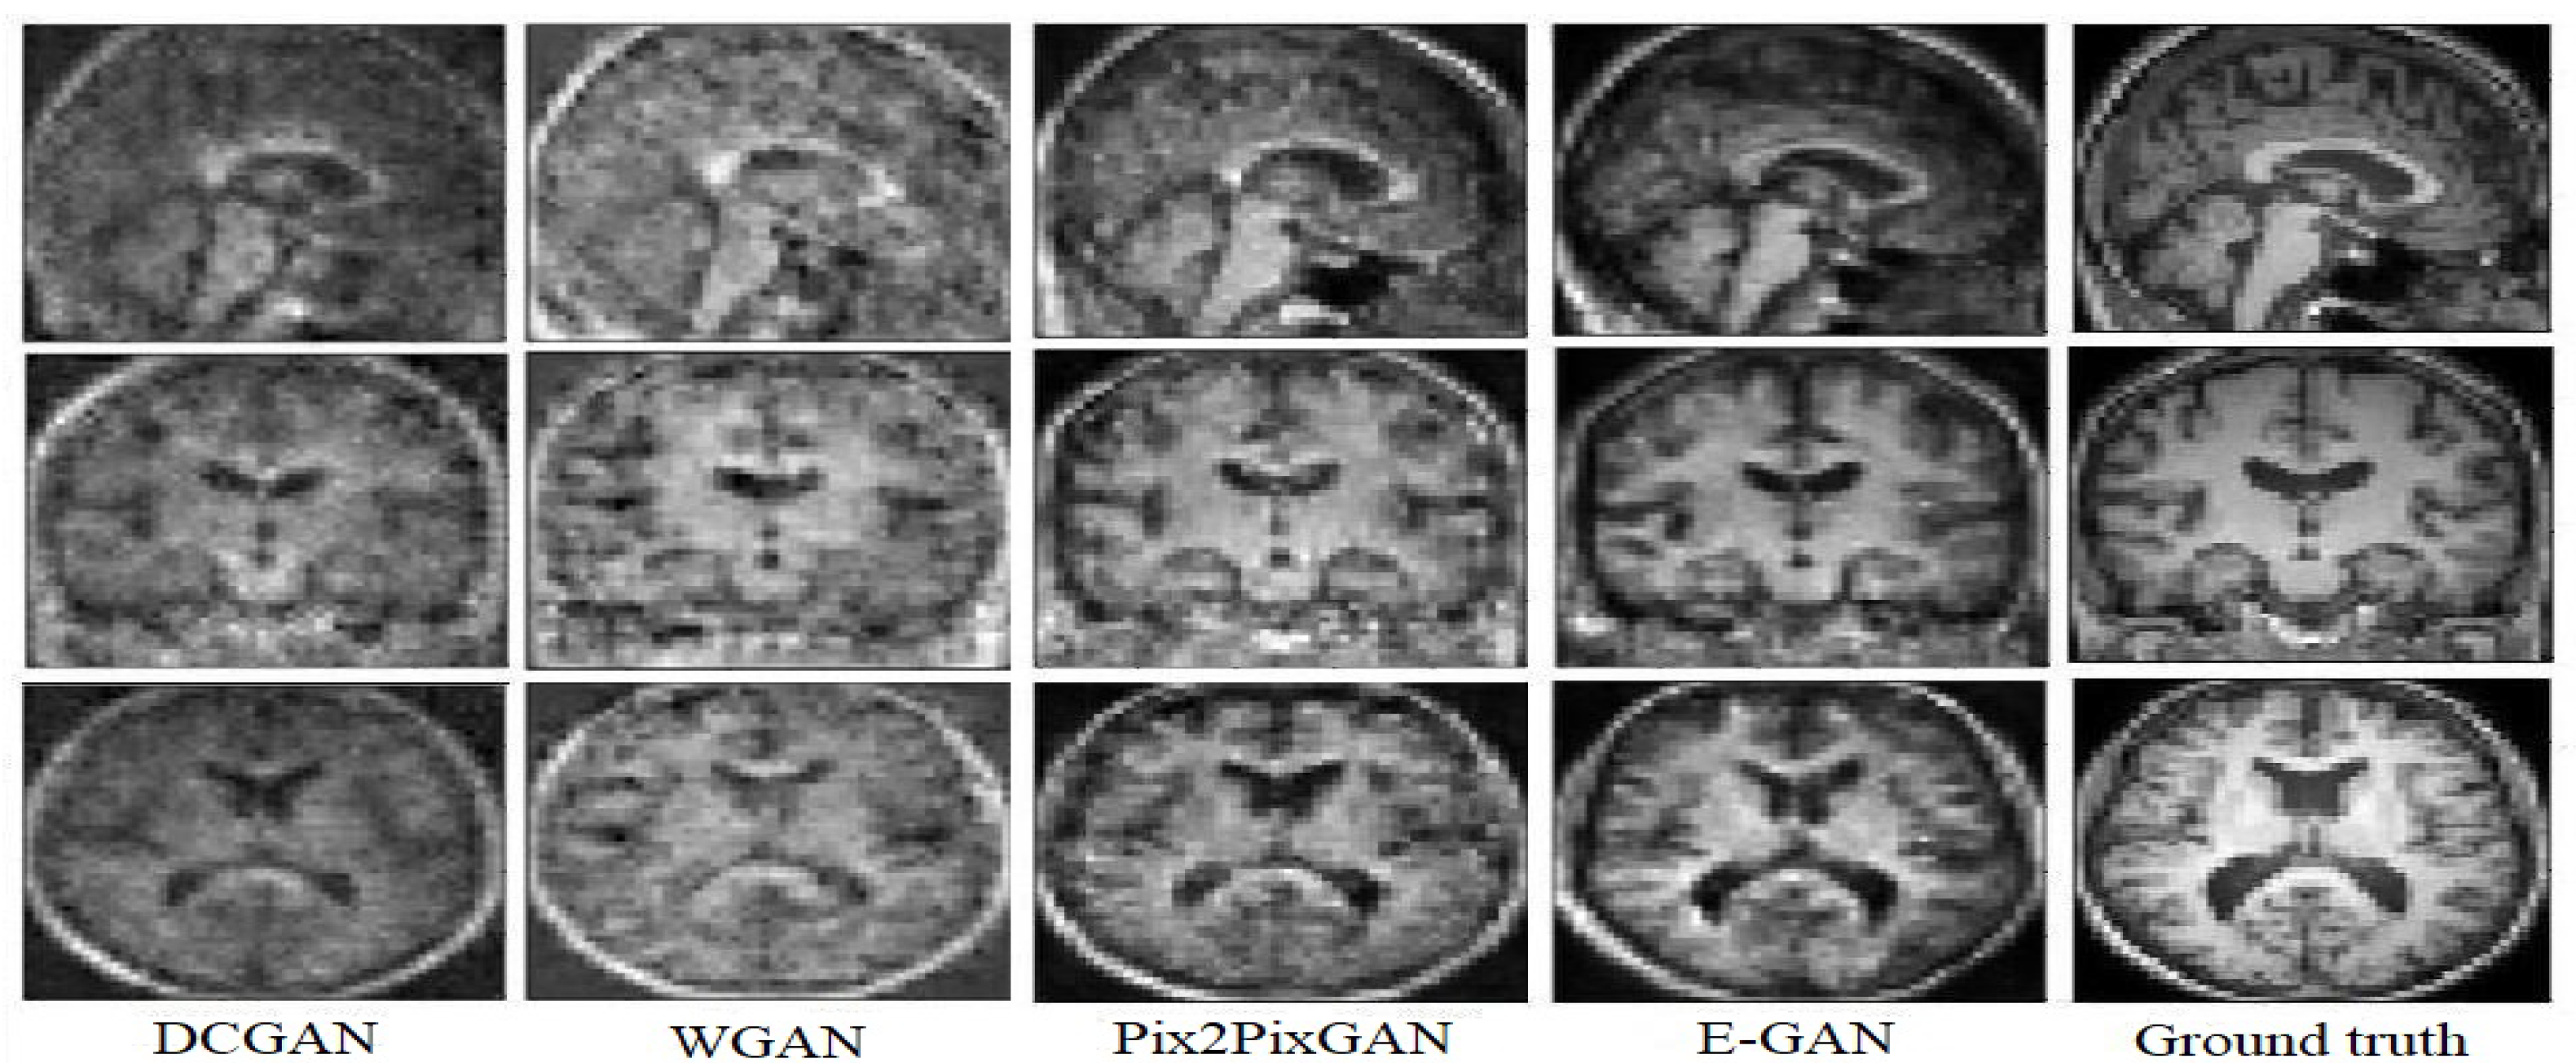

Figure 5.

Experimental results for translating PET images to corresponding MRI with 3D DCGAN [35], 3D WGAN [25], 3D Pix2Pix GAN [17], and the proposed method.

According to Figure 5, WGAN and DCGAN are defeated by Pix2Pix GAN and the proposed model in terms of visual assessment. The proposed method has higher quality and almost no artifacts and blurriness compared to Pix2Pix GAN.

The DCGAN almost could not generate the uniform tissues and the generated image only has the main structure of the T1 weighted MRI. While the synthetic result of the WGAN has a better performance on synthesizing the structure of T1 weighted MRI, the synthetic images often preserve noise. The Pix2Pix GAN architecture obtains more details inside the tissues but both the Pix2Pix GAN and the WGAN performed poorly for the boundaries and sometimes visual artifacts in the corner of the synthetic images. E-GAN shows a good performance in terms of generating boundaries and edges.